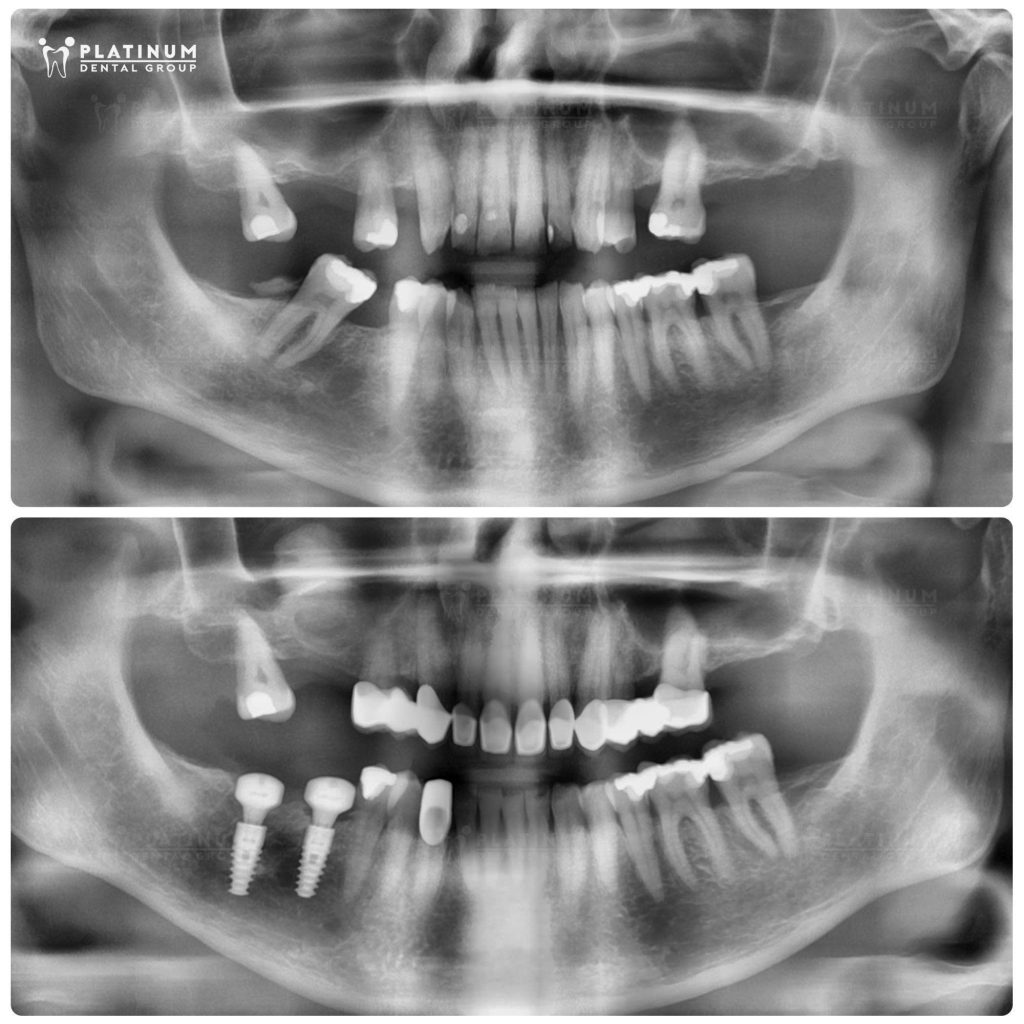

Following a thorough clinical assessment and professional consultation, our team developed a multidisciplinary treatment plan focused on three key goals:

Dr. Duong Minh Tung

Performed the sinus lift, bone grafting, and dental implant placement in the areas where the molars had been lost.

Dr. Quoc Duy

Restored the heavily damaged teeth with porcelain crowns and refined the smile line for a more balanced appearance.

From the planning stage onward, every step was carefully coordinated to ensure that the implants and final restorations worked in harmony. This allowed us to rebuild a bite that felt stable, comfortable, and durable giving Mr. Jeffrey the confidence to return home and enjoy daily life with greater ease.